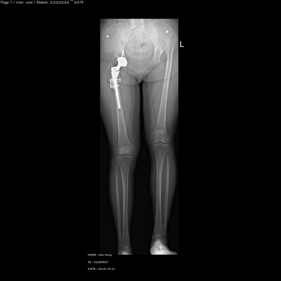

- total hip replacement on hips with u…

- rivision total hip replacement for d…

shortening osteotomy and total hip replacement for bilateral severe dysplasia of hip with high riding